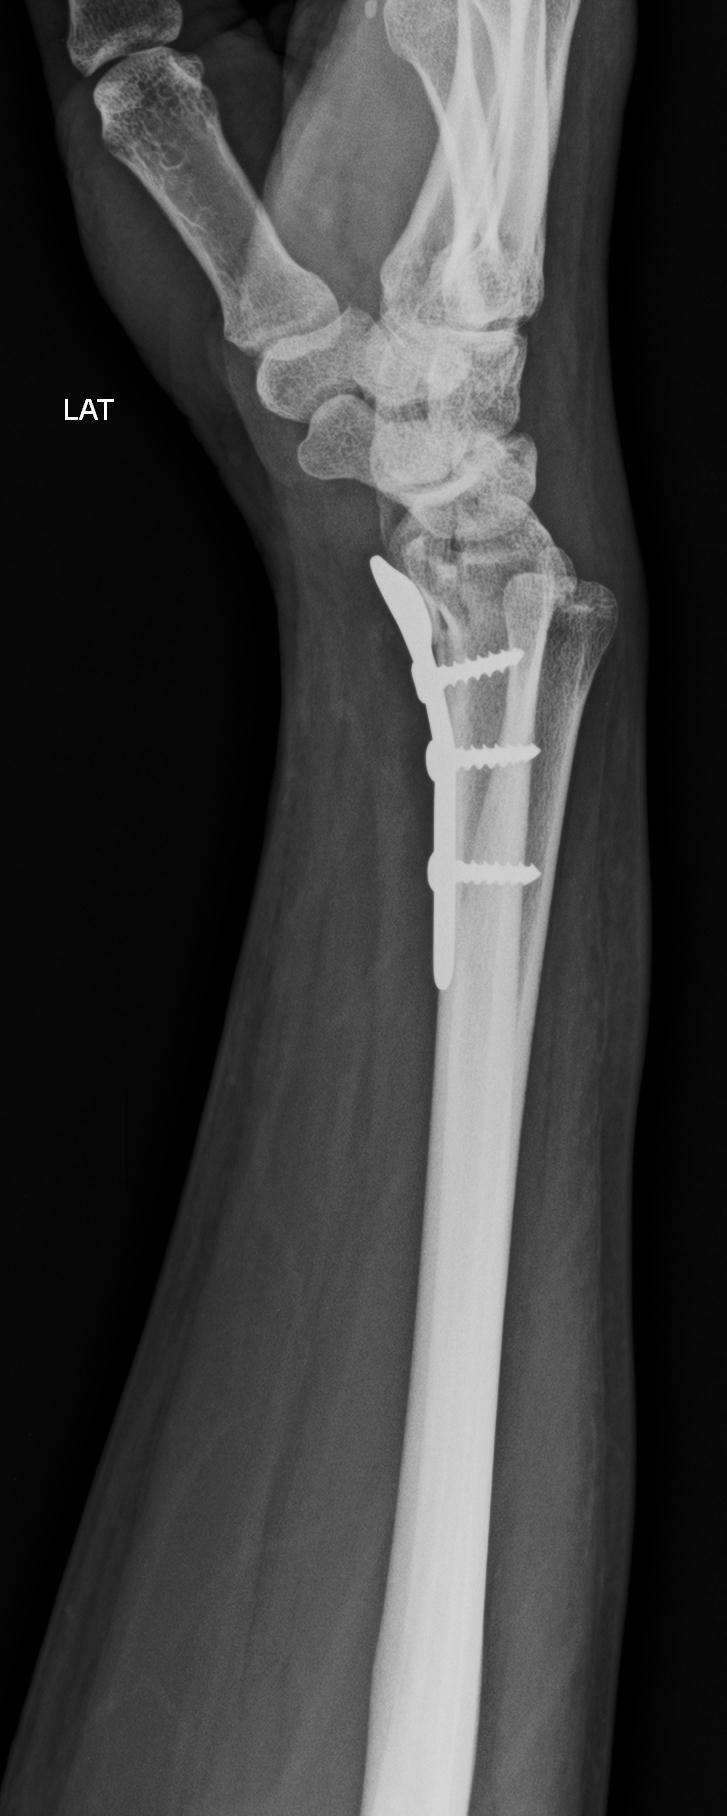

Dr Kamran Saeed is a well known and extremely experienced orthopedic and trauma surgeon of Lahore, Pakistan .